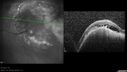

INDOCYANINE GREEN ANGIOGRAPHY: Indocyanine green angiogram of the left eye was obtained, which does show hypofluorescence in the area of the lesion. There do appear to be some vessels within the lesion, but only minimally.

B-SCAN ECOGRAPHY: B-scan ecography of the ultrasound of the left eye shows a dome-shaped lesion, which is 9x9 millimeters with low internal reflectivity.

A-SCAN ECOGRAPHY: The A-scan confirms low internal reflectivity with a height of 4 millimeters at the peak on the lesion.